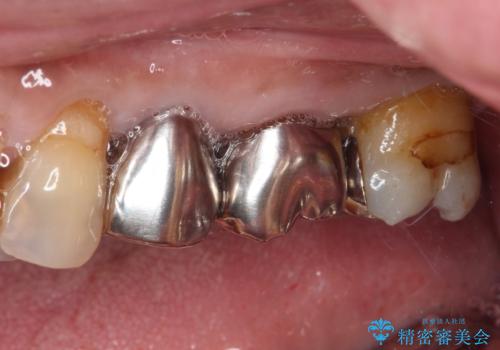

- 詰め物が欠けてしまい、虫歯かもしれないから診てほしいとのことで来院された患者様です。

精査の結果、詰め物の下に虫歯が大きく広がっているのがわかりました。

虫歯の範囲が大きく、部分的な詰め物では対応が難しいため、オールセラミッククラウンにて補綴することとしました。

外見からはあまり大きな虫歯があるようには見えなくても、X線検査をすることで、詰め物の下に虫歯が広がっていることは多々あります。